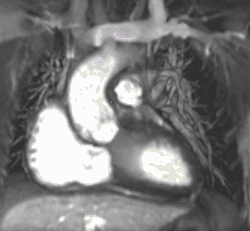

Myocardial infarction. Imaging in the 4-chamber plane. Left: Inversion recovery LGE sequence. Right: Corresponding cine sequence. This shows a chronic infarction with akinetic apex and transmural scar. Mitral regurgitation is also present.